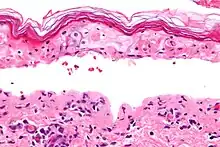

Histology

Definitive diagnosis of TEN often requires biopsy confirmation. Histologically, early TEN shows scattered necrotic keratinocytes. In more advanced TEN, full thickness epidermal necrosis is visualized, with a subepidermal split, and scant inflammatory infiltrate in the papillary dermis. Epidermal necrosis found on histology is a sensitive but nonspecific finding for TEN.[7]

Confluent Epidermal Necrosis, low mag

Confluent Epidermal Necrosis, high mag